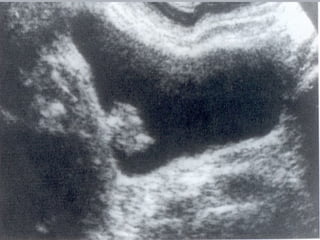

Câncer de Bexiga Estudos de imagens Diagnóstico Ultrassonografia Urografia excretora Estadiamento CT RNM Rx tórax  Cistoscopia + biópsia + biópsias randomizadas

Câncer de BexigaEstudos de imagens Diagnóstico Ultrassonografia Urografia excretora Estadiamento CT RNM Rx tórax Cistoscopia + biópsia + biópsias randomizadas